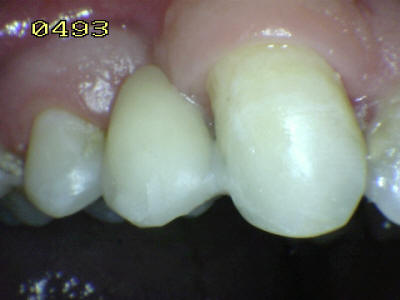

Observe la adaptación del

metal al esmalte de este puente Maryland que repone la

pieza dental 24